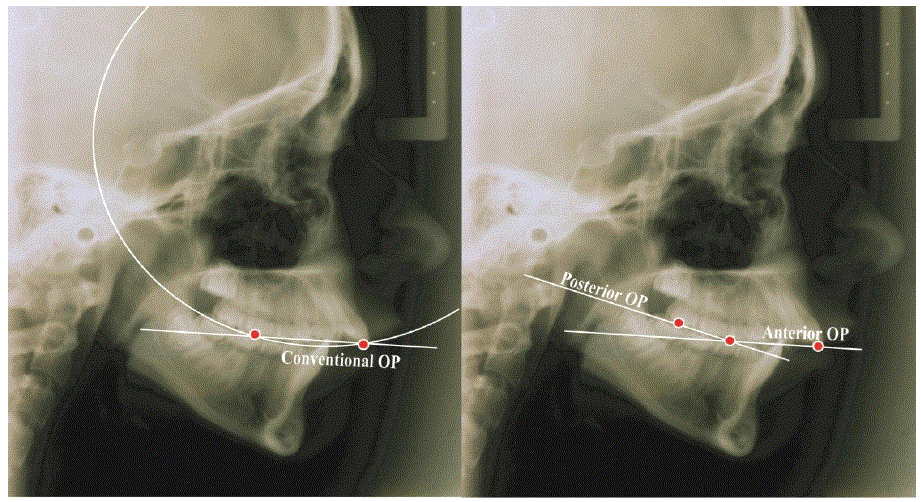

图1和2:常规咬合面和POP和AOP [24]之间的差异。

最重要的是咬合和下颌平面OP-MP [14]之间的角度。通常,OP-MP角度保持恒定[15,16]。然而,咬合平面[17],下颌骨的一个向后转动的过度位移期间[18]发生,这导致增加了OP-MP角[19]。此外,咬合平面的过度位移的另一个实例中有不充分的垂直支撑闭塞[20,21],并因此限制生长[22,23](图1-4)的下颌骨髁突停留的。

上前咬合平面(UAOP)[24]是由与上部第二前磨牙的尖端连接上中切牙的前端建立。

上后咬合平面(Upper Posterior occlusion Plane, UPOP)[24]用连接上第二前磨牙杯与上第二磨牙咬合面的连线表示。